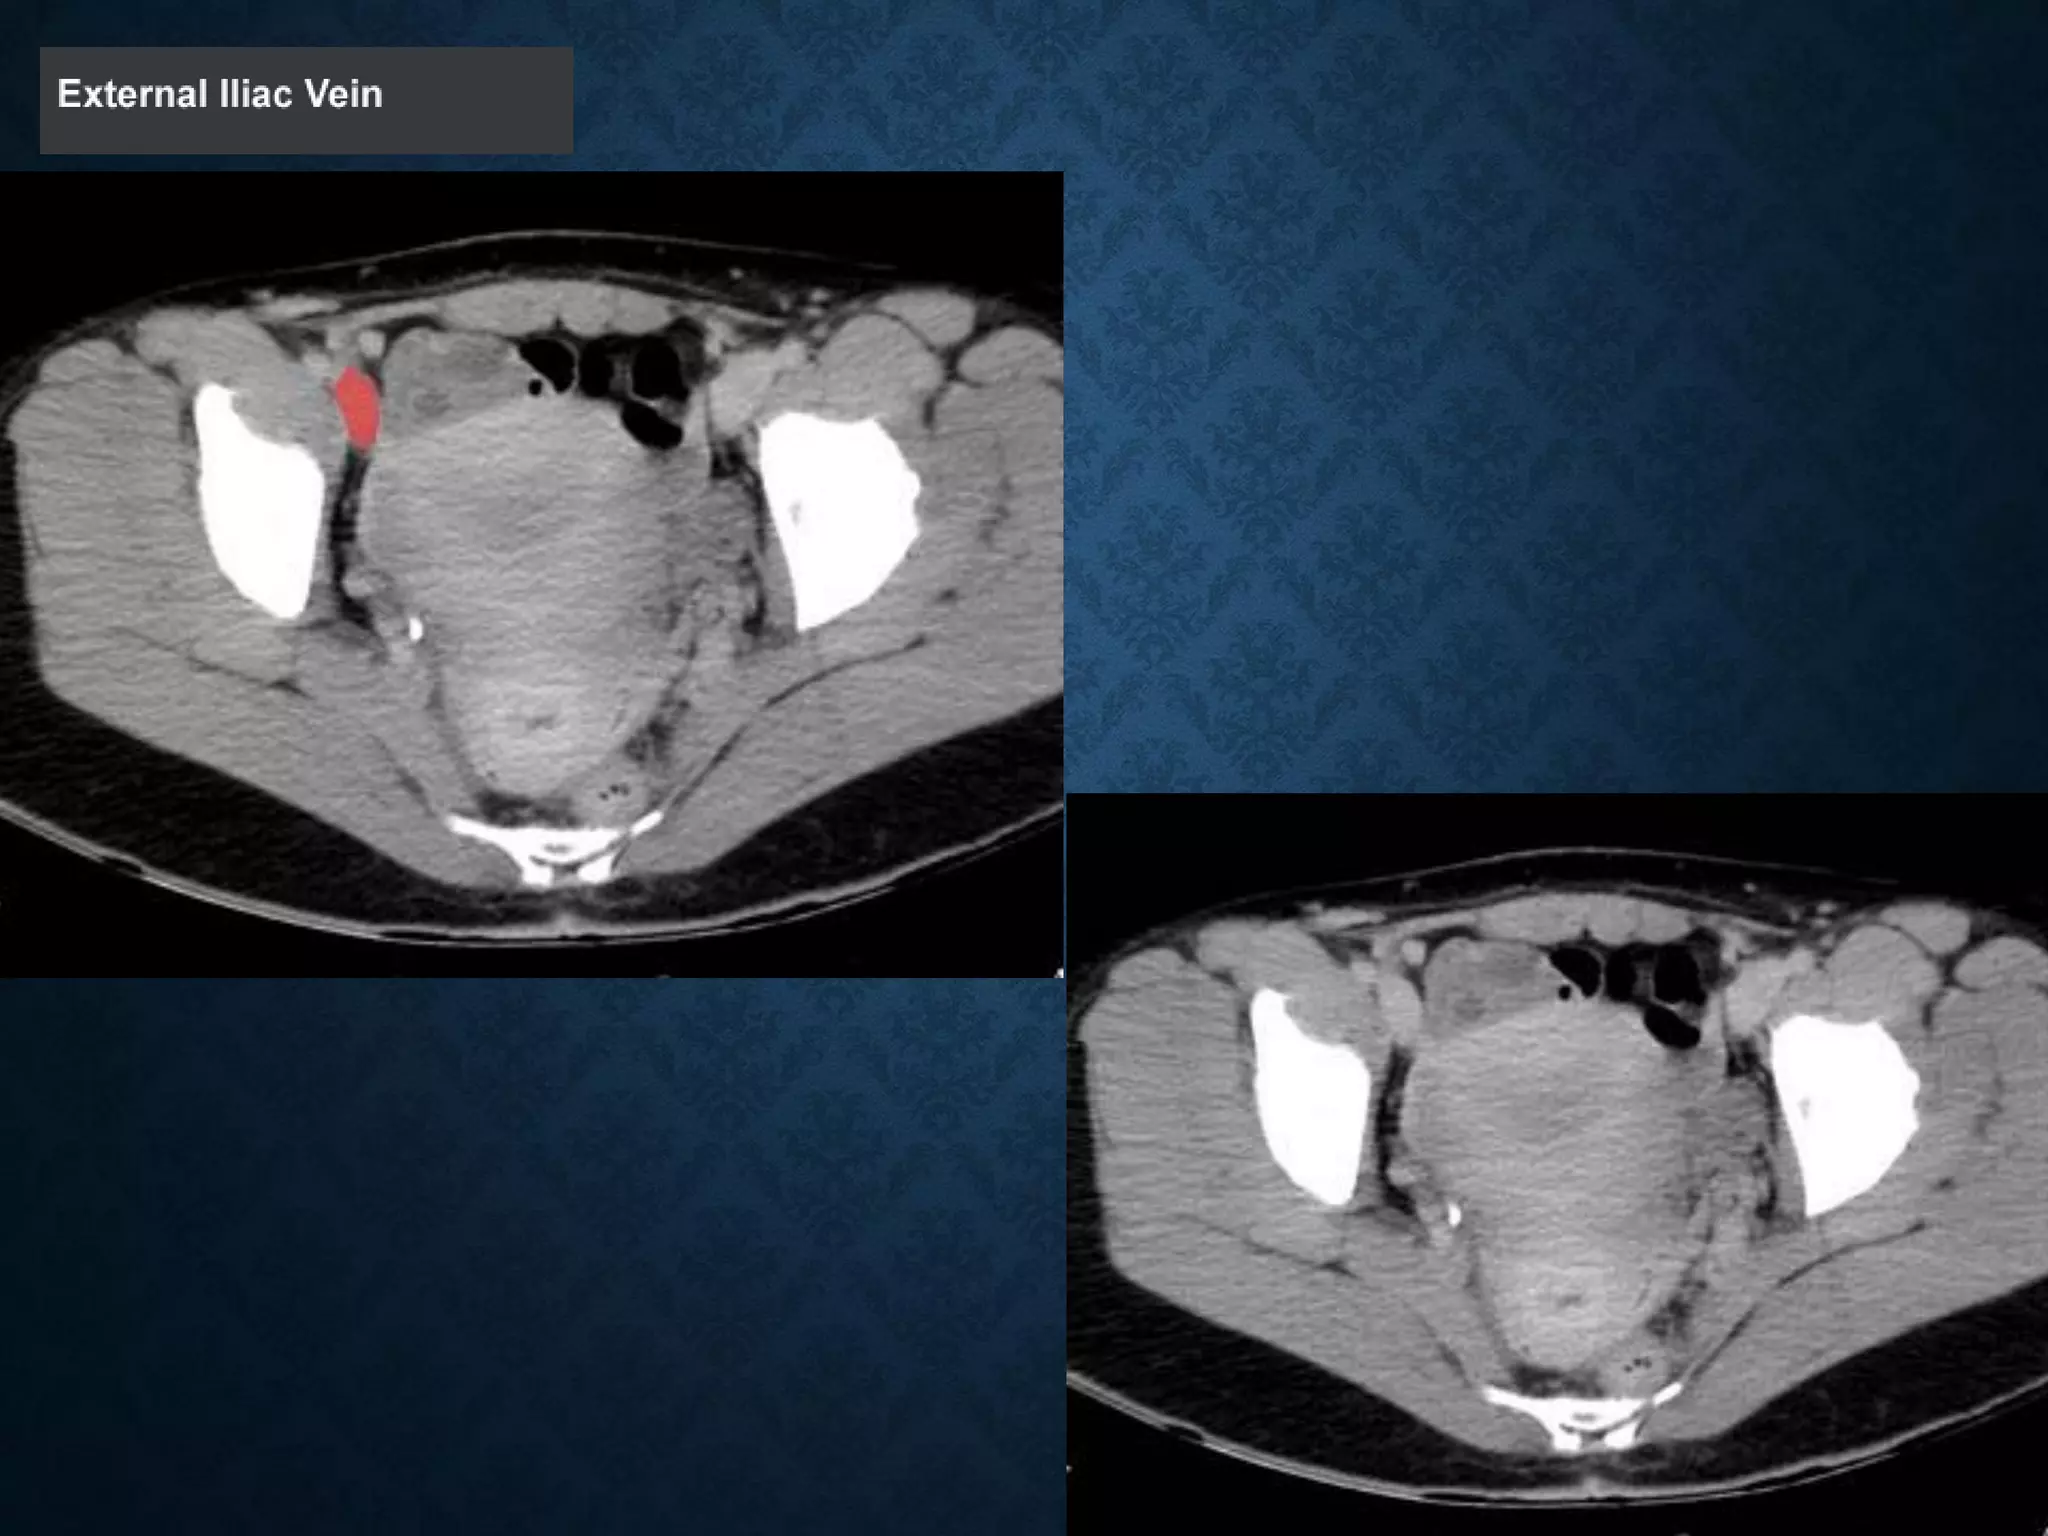

INGUINAL LIGAMENT